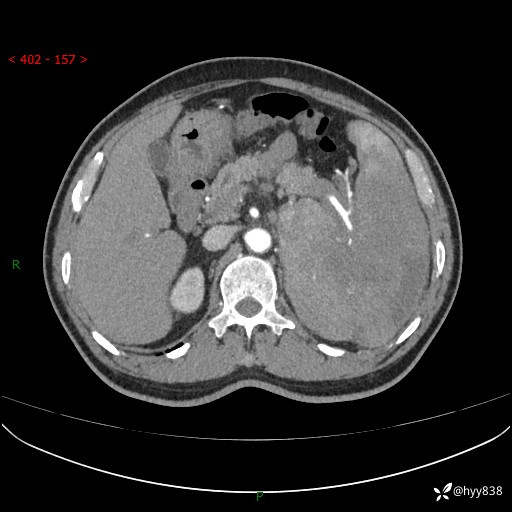

上腹部CT平扫

增强(动脉期+静脉期)